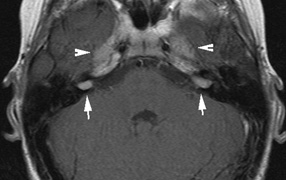

Mental retardation and seizures in TSC are often associated with benign CNS astrocytic hamartomas.131 On imaging, the cerebral lesions show three patterns:132

1. Superficial cortical sclerosis (parenchymal hamartoma) which distort the gyri. Microscopy shows large atypical fibrillary type astrocytes with few associated neurons and areas of calcification.133 The numerous abnormal glial processes and fibers make the tissue abnormally firm or “sclerotic” on palpation (Fig. 13).132

2. Subependymal nodules (SEN) are typically found along the lateral borders of the ventricles and parehncymal brain lesion (“cortical tubers”) (Figs. 14 and 15). Calcification in the first year of life is rare.132

3. White matter abnormalities are a characteristic “ventriculofugal” pattern corresponding to the embryological migratory paths of neurons and glia. These lesions may represent aberrant neuronal migration, a possible reflection of haploinsufficiency for the TSC gene.116,132,134

On MRI imaging, the subependymal nodules and parenchymal brain lesions of infants (age ≤3 months) and adults show different signal characteristics. Infant CNS tubers are hyperintense on T1-weighted images and hypointense on T2-weighted images, which is the opposite of the pattern seen in adults.134 Malignant transformation of SEN occurs in about 10% to 15% of patients and the resultant subependymal giant cell astrocytoma accounts for 25% of premature deaths in TSC.135,136

Fig. 15. Tuberous Sclerosis Complex. (a) Patient 1: Axial CT scans demonstrating typical calcification of subependymal nodules in a 13-year-old girl with a history of seizures. (b and c) Patient 2. (b) Axial T2-weighted images demonstrate calcified subependymal nodules (arrowheads) and cortical tubers typical of tuberous sclerosis. (c) Widespread cortical tubers are seen on a coronal FLAIR sequence as thickening of the cortex and high signal of the subcortical white matter.